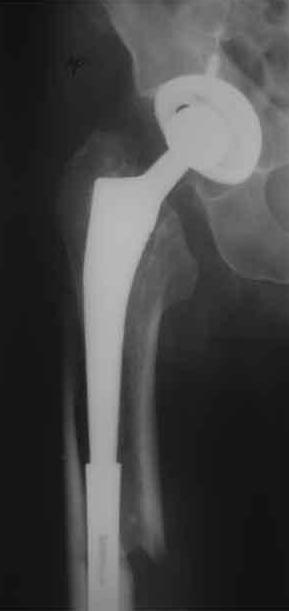

Произведено закрытое удлинение ножки эндопротеза с помощью ретроградного интрамедуллярного стержня. Продолжительность операции 3 часа. Два из них закрытое восстановление длины бедра диистрактором

таз-бедро.